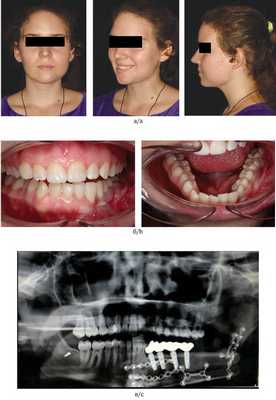

Пациентка Б., 18 лет, поступила с диагнозом: амелобластома нижней челюсти слева (плексиморфная форма) (рис. 7). Рис. 7. Пациентка Б. (18 лет) до операции. а — внешний вид; б — внутриротовая съемка. План операции включал проведение тщательного планирования, интраоперационное удаление новообразования, подъем и моделирование реваскуляризированной малой берцовой кости с внедрением в зубосодержащий фрагмент дентальных имплантатов и протезной конструкции. Пациентке был выполнен забор фрагмента икроножного нерва. После аноксии лоскута аутотрансплантат фиксировался в реципиентной области с установкой зубов в окклюзию и осуществлялась реваскуляризация трансплантата через сосуды шеи (рис. 8). Рис. 8. Этапы реконструкции субтотального дефекта нижней челюсти пациентки Б. (18 лет).

Пациентка Б. была эстетически и функционально реабилитирована с полным восстановлением зубочелюстной системы и чувствительности по ходу нижнелуночкового нерва (рис. 9). Рис. 9. Результат комплексного лечения пациентки Б. (18 лет) через 8 мес. а — внешний вид; б — внутриротовая съемка; в — рентгенография. Срок наблюдения составил 8 мес.